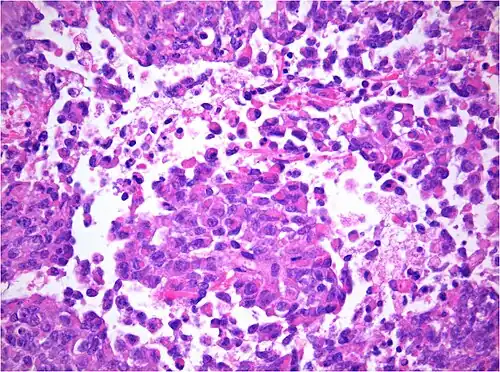

-

AT/RT Histology with numerous rhabdoid tumor cells -

AT/RT and rhabdoid tumor share the term "rhabdoid" because under a microscope, both tumors resemble rhabdomyosarcoma.

The tumor histopathology is jumbled small and large cells. The tissue of this tumor contains many different types of cells including the rhabdoid cells, large spindled cells, epithelial and mesenchymal cells, and areas resembling primitive neuroectodermal tumor (PNET). As much as 70% of the tumor may be made up of PNET-like cells. Ultrastructure characteristic whorls of intermediate filaments are seen in the rhabdoid tumors (as with rhabdoid tumors in any area of the body). Ho and associates found sickle-shaped embracing cells, previously unreported, in all of 11 cases of AT/RT.[24]